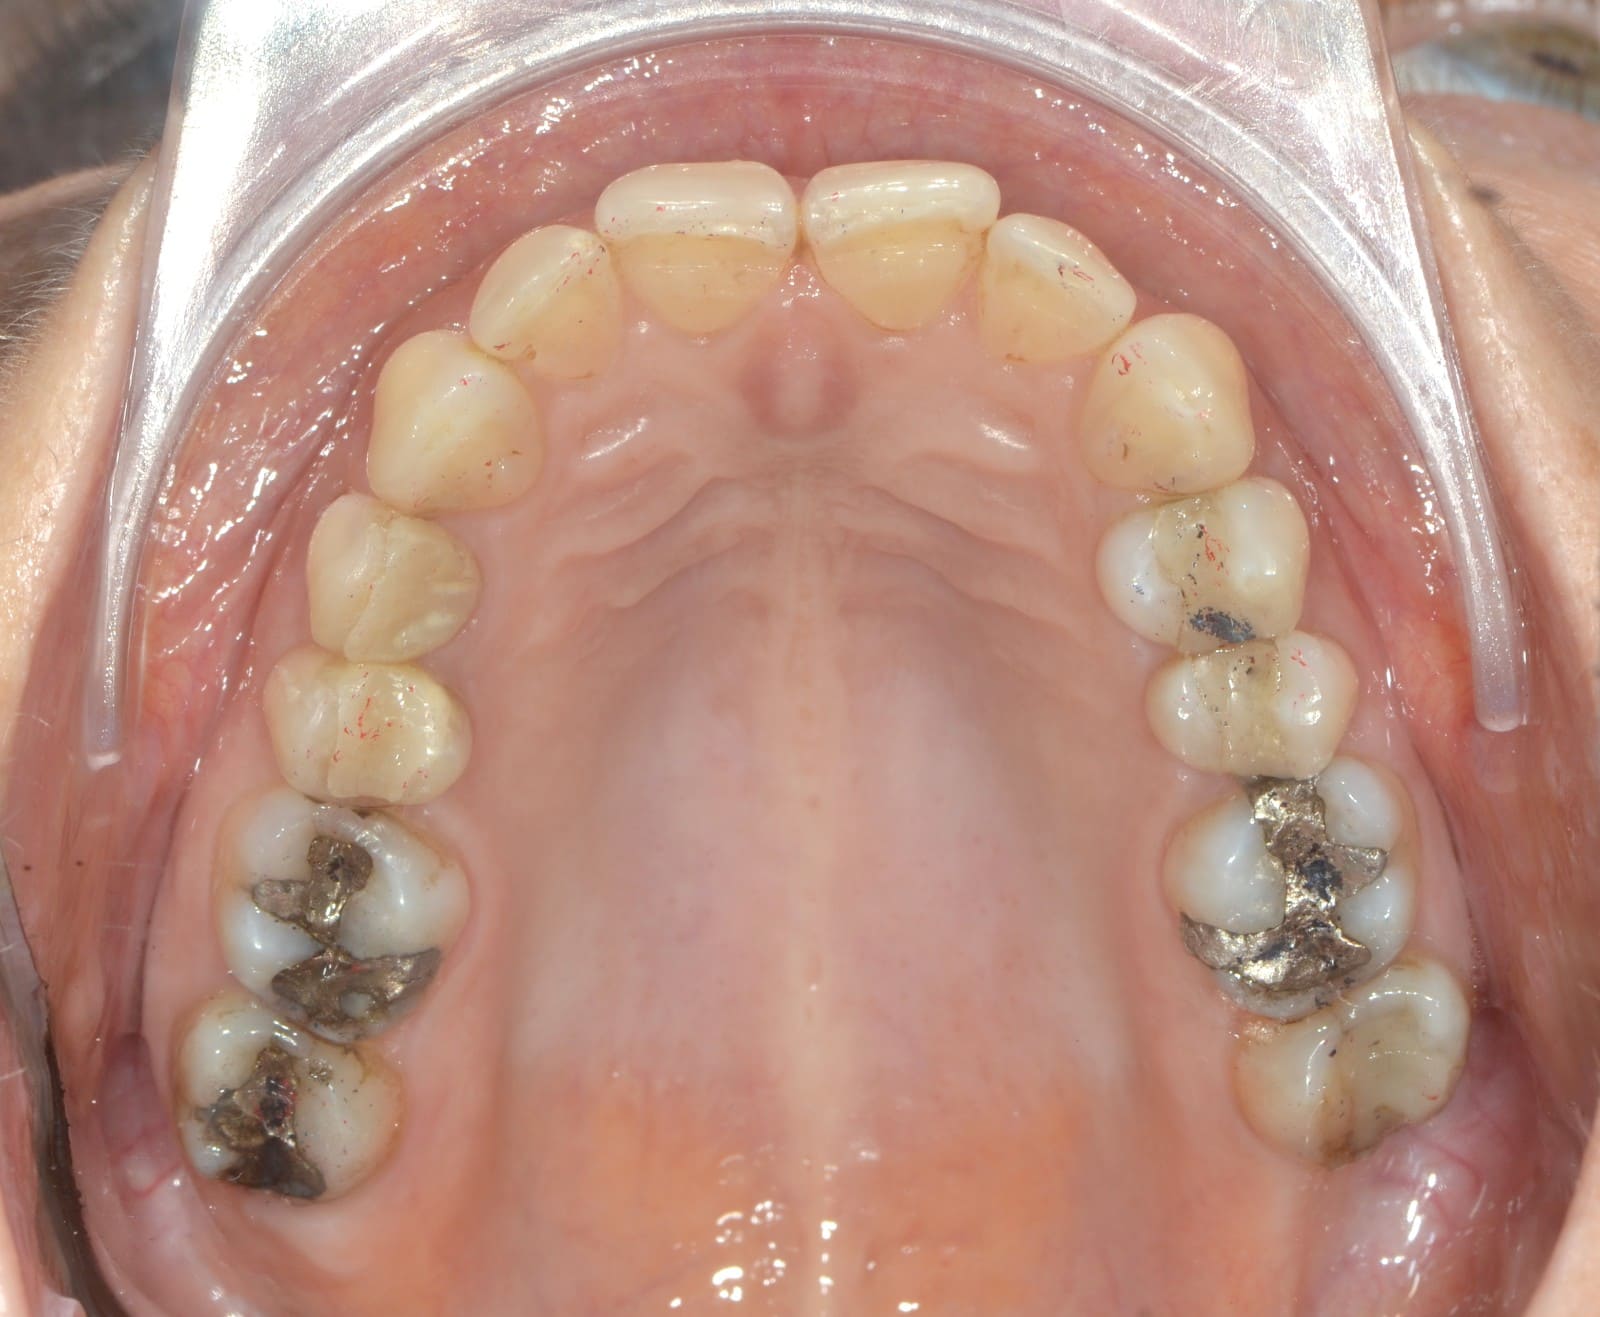

Initial